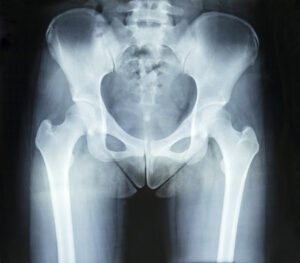

Kıkırdak dokunun tamamen yıpranması sonucu şiddetli ağrı ve hareket kısıtlılığı oluşur. Bağışıklık sisteminin eklemlere saldırması nedeniyle kalça eklemi tahrip olabilir. Özellikle yaşlı bireylerde kalça kırıkları ciddi hareket sorunlarına yol açabilir ve protez ile kalıcı çözüm sağlanabilir.

Kalçanın anormal gelişimi nedeniyle zamanla eklem aşınması ve ağrı meydana gelebilir. Kan akışının azalması sonucu kalça kemiğinde çökme yaşanabilir ve protez ameliyatı kaçınılmaz hale gelebilir.

Ameliyat öncesinde hastanın genel sağlık durumu değerlendirilir ve gerekli tetkikler yapılır. Kan testleri, röntgen, MR ve EKG gibi testlerle hastanın ameliyata uygun olup olmadığı belirlenir. Kalça protezi ameliyatı genellikle genel veya spinal anestezi altında yapılır. Cerrah, hasarlı kalça eklemini çıkararak yerine uygun boyutta bir protez yerleştirir. Bu işlem yaklaşık 1-2 saat sürer. Protezin kemiğe sabitlenmesi çimentolu veya çimentosuz yöntemlerle yapılabilir. Ameliyat sonrası hastalar genellikle 2-5 gün hastanede kalır. İlk günlerde hafif hareketlerle rehabilitasyona başlanır. Hasta, fizik tedavi uzmanları eşliğinde yürümeye teşvik edilir.